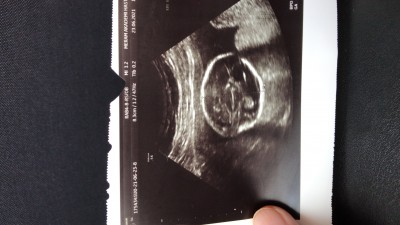

image

Buda bizim bacak aramız cinsiyetimiz kız ama erkek diyende oldu kız diyende oldu artık doğumu bekliyoruz

Net bsy yok yani daha ortada kordon bağı olabilir mi acaba o cikinti